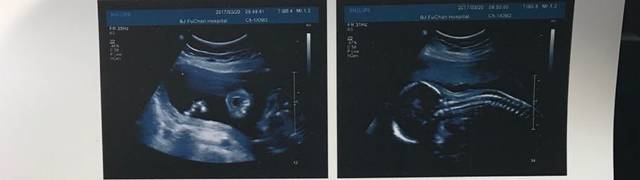

请慧眼识别一下,17周宝宝b超图!